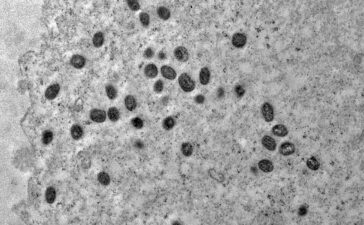

Ministério investe R$ 3 milhões em pesquisas sobre varíola do macaco

O Ministério da Ciência, Tecnologia e Inovações informou que vai investir R$ 3 milhões em projetos de pesquisa científica sobre...

O Brasil ultrapassou, ontem, a marca de 4 mil casos confirmados de varíola dos macacos (monkeypox), um acúmulo de 160...